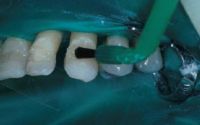

El composite se coloca en el canal lingual utilizando la punta de los carpules, el composite fluirá suavemente dentro del mismo.

Ribbond se inserta dentro del canal relleno de composite comenzando por el extremo distal del canal o el canino, presionando la fibra Ribbond dentro del composite. Al realizar este procedimiento el sobrante de composite rebasara. Se alisara y retirara el exceso de las superficies linguales antes de polimerizar. Se polimerizara las superficies linguales durante 60 segundos por diente.

Después de retirar cualquier irregularidad del composite polimerizado, las superficies de la restauración suavizarse. Esto se logra con una resina de composite fluido dispensado con una jeringa con punta de aguja. Se polimerizara la superficie lingual durante 40 segundos por diente.

A causa de la oclusión tan ajustada, la férula se colocó en la superficie vestibular con una preparación de canal. Este se realizó utilizando una fresa de 330 con una profundidad de entre 0,5 y 1 mm y extendiéndose desde la mitad mesial del primer premolar hasta el incisivo central. La anchura de 2 mm del canal se determina por el ancho de 2 mm de la fibra Ribbond. Se grabaron los dientes durante 30 segundos, se enjuagaron y se secaron. Se aplicó el adhesivo en las superficies grabadas. No polimerizar hasta colocar el composite.

En la superficie vestibular se aplicó un composite hibrido de viscosidad media. La fibra Ribbond se colocó en el centro del canal presionándolo contra el composite, se retiró el exceso de este antes de la fotopolimerización